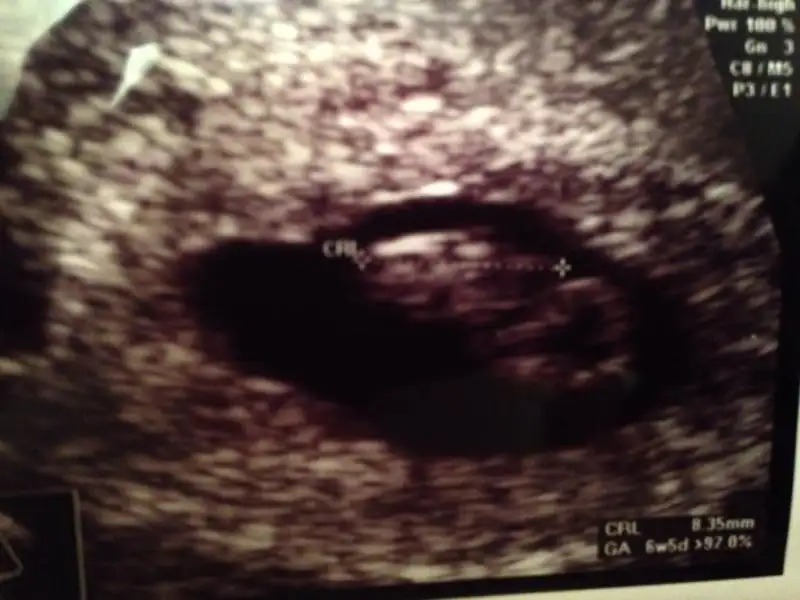

Kizlar 6+3 iken cekilen usg de fotoda daha yolk kesesi gorunuyor bebis ortada kalmis amavideo cekmistik kalpatislari icin ayni gun ve o videoda ultrason ekraninda kese fasulye seklinde ve bebisim sol tarafa yapisik duruyo hangisini baz alsam bilemedim

Bu da bizim 8+1 5 gün önden gidiyor. Oglumda fasulye gibi kesesi bunda yuvarlak...